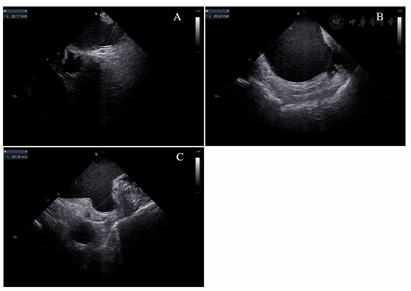

在局部麻醉下穿刺双侧股静脉,经左侧股静脉通路置入6 F静脉血管鞘,沿鞘送入10级可调弯冠状窦电极,经右股静脉通路分别置入2根8.5 F Swartz长鞘,使用Brockenbrough针行两次房间隔穿刺。静脉注射肝素,使ACT维持在300~350 s。在导丝引导下将Swartz鞘送入左房,撤出导丝和Brockenbrough针,经Swartz鞘分别放入Lasso环状标测电极(美国强生公司)和Smarttouch压力消融导管(美国强生公司)。在Carto 3D三维标测系统(美国强生公司)指导下,使用Lasso电极构建左房和肺静脉的三维解剖模型,放置Lasso电极于左右肺静脉口部,消融电极沿左右肺静脉行环肺静脉电隔离,终点为肺静脉内与左心房传导双向阻滞。消融后患者心律仍为房颤心率,给予双向150 J同步直流电复律后转为窦性心律。观察20分钟,反复心房程序刺激未诱发房性心动过速,再次验证四支肺静脉电位未恢复,房颤消融手术成功。撤出Lasso电极,换11 F鞘管,将ICE电极经鞘管送入左房,分别以45°、90°和135°测量左心耳口部直径分别为20.77、20.62、20.19 mm,深度为24.23、25.28、24.37 mm(图1)。与术前经食道超声所测的左心耳大小数据相似度较高。留置导丝至左上肺静脉,退出鞘管,经导丝送入14 F Watchman输送鞘至左心房,经鞘管和导丝送入5 F猪尾导管至左房,退出导丝调整猪尾导管至左心耳,右前斜30°、足位20°造影显示左心耳形态为单分叶风向袋型,测量口部直径为21.62 mm,深度为24.83 mm,推送鞘管至左心耳内,退出猪尾导管,经鞘管推送27 mm的Watchman(美国波士顿科学)封堵器至左心耳,经X线核实位置后,缓慢释放封堵器,X线造影和ICE核实封堵器位置良好,45°、90°和135°测量均无残余分流、无露肩(图2),压缩比分别为20%、22%、20%。封堵器牵拉试验未见移位及脱落,逆时针旋转输送器并释放封堵器。观察10 min,ICE复查封堵器位置,再次测量残余分流、露肩和压缩比,与释放前相比各角度均无明显变化(图3)。术中ICE测量无嵴水肿、无心耳旁积液、无心包积液,左心耳封堵手术成功。房颤导管消融及左心耳封堵手术时间为103 min,透视剂量为356 mGy。